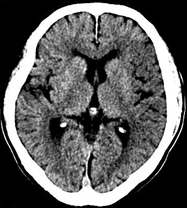

如上圖所示,相鄰的三張軸位圖像未見(jiàn)明顯異常,根據(jù)傳統(tǒng)軸位圖像很難得到準(zhǔn)確的臨床診斷。